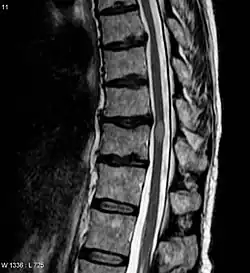

MRI image of transverse myelitis patient's spinal cord

Myelitis lesions usually occur in a narrow region but can be spread and affect many areas.